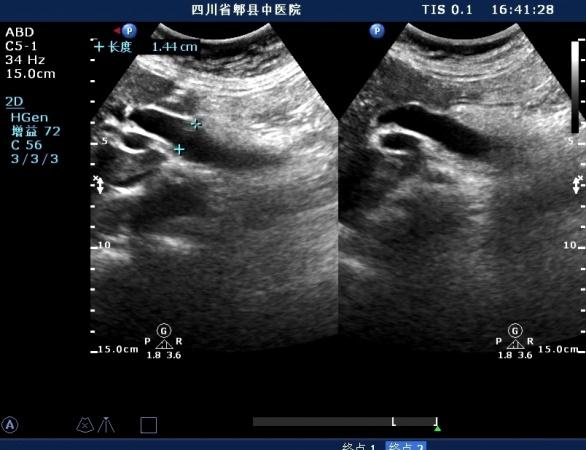

女,70岁,外伤入院就诊,皮肤未见明显黄疸,自述胆囊已切除

超声如图:胆总管及肝内胆管扩张,呈“平行管征”,胆总管胰腺段可见疏松强回声团堆积,后方可见淡淡声影,左肝外叶胆管内亦可见数个强回声团堆积,后方伴声影。 肝脏及胆总管

扩张的胆总管

扩张的左肝内胆管

扩张的右肝内胆管